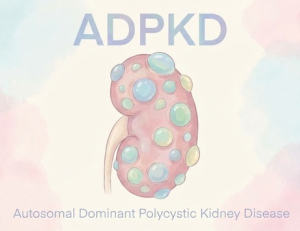

- [ForDoc Health] 유전자의 침묵하는 위협, 상염색체 우성 다낭성 신장병(ADPKD)의 모든 것

- 신장은 우리 몸의 노폐물을 걸러내는 정수기 역할을 하는 중요한 장기다. 그러나 이 고요한 장기 속에 수많은 물집(낭종)이 포도송이처럼 생겨나 서서히, 그리...

- 2025-12-19